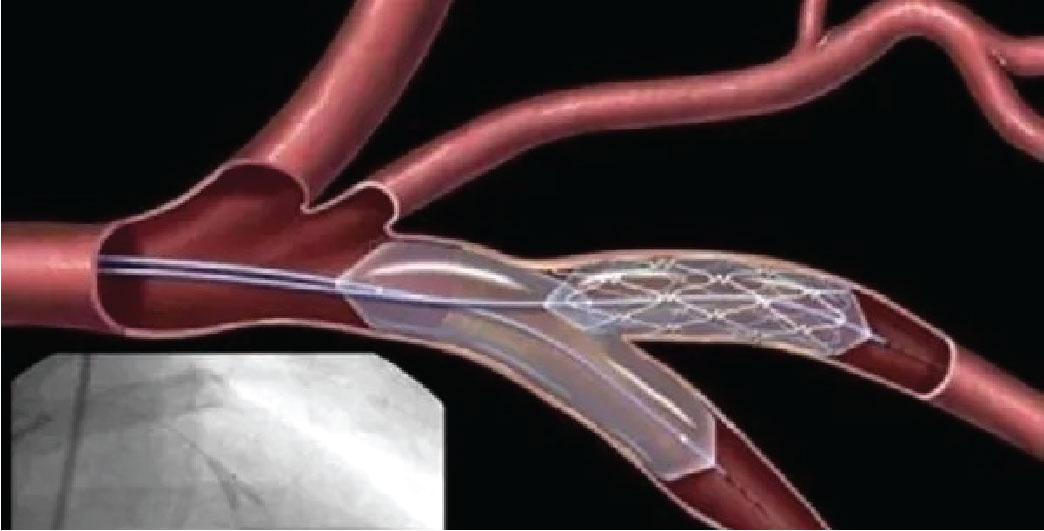

হার্টের রিংয়ের নতুন মূল্য নির্ধারণ করে দিয়েছে ঔষধ প্রশাসন অধিদপ্তর। কিন্তু এক্ষেত্রে চরম বৈষম্য সৃষ্টি করা হয়েছে। যুক্তরাষ্ট্রের তিন কোম্পানির ক্ষেত্রে ‘মার্কআপ ফর্মুলা’ অনুসরণ করা হলেও রিং সরবরাহকারী ইউরোপের ২৪টি কোম্পানিকে এ তালিকায় রাখা হয়নি। অর্থাৎ, যুক্তরাষ্ট্রের তিন কোম্পানি দাম কমিয়েছে সামান্য আর ইউরোপের ২৪ কোম্পানির দাম কমিয়েছে কস্টিং খরচের চেয়ে কম। দাম নির্ধারণে বৈষম্যের অভিযোগ এনে সরবরাহকারী ব্যবসায়ীরা ধর্মঘট করছে।

ইউরোপের দেশগুলো থেকে রিং আমদানিকারক ২৪ প্রতিষ্ঠান গত ১২ দিন ধরে এসব সরঞ্জাম বিক্রি বন্ধ রেখেছে। পুনরায় মূল্য সমন্বয় না হওয়া পর্যন্ত শুধু সংকটাপন্ন রোগী ছাড়া হাসপাতালগুলোতে রিং সরবরাহ ও অন্যান্য রোগীদের কাছে বিক্রি করা হবে না বলে জানিয়েছে তারা। মূল্য পুনর্নির্ধারণ করে দ্রুত সমাধান চেয়েছে আমদানিকারকরা।

সংশ্লিষ্টরা জানান, দীর্ঘদিন ধরে হার্টের মূল্য নিয়ে কালোবাজারি চলছে। এটা নিয়ন্ত্রণ করতে প্রশাসন ব্যর্থ হয়েছে। নেপথ্যে অর্থের লেনদেনের অভিযোগ রয়েছে। এতে আর্থিকভাবে ক্ষতিগ্রস্ত হচ্ছে রোগীরা। লাগাম টানতে মূল্য নির্ধারণের নামে বৈষম্য সৃষ্টি করে রোগীদের নতুন করে ভোগান্তিতে ফেলেছে প্রশাসন। রিং বিক্রি বন্ধ থাকায় সেবা না পেয়ে ফিরে যাচ্ছেন রোগীরা। হার্টের রিংয়ের নতুন মূল্য

হার্টের স্ট্যান্টের দাম পুনর্বিবেচনা করার দাবিতে ২৪টি কোম্পানির প্রতিনিধিদল মঙ্গলবার ঔষধ প্রশাসন অধিদপ্তরের মহাপরিচালক মেজর জেনারেল মোহাম্মদ ইউসুফের সঙ্গে দেখা করেন।

তারা জানান, ডলারের দাম বৃদ্ধিতে আমদানি খরচ বেড়ে যাওয়ায় আগের মূল্যে বিক্রি সম্ভব হচ্ছে না। কিন্তু আলোচনায় কোনো সুরাহা হয়নি। আরও আলোচনা করতে আগ্রহী ঔষধ প্রশাসন।

ব্যবসায়ীরা জানান, সঠিক আশ্বাস না পাওয়ায় স্ট্যান্ট বিক্রি বন্ধ থাকবে। তবে মানুষের খুবই ইমার্জেন্সিতে বিক্রি করা হবে। ঔষধ প্রশাসন অধিদপ্তরের কর্মকর্তারা বলেন, জাতীয় মূল্য নির্ধারণ কমিটির পরামর্শেই হার্টের রিংয়ের নতুন দাম বেঁধে দেওয়া হয়েছে। তবে খোঁজ নিয়ে জানা গেছে, দাম নির্ধারণে কমিটির অর্ধেকের বেশি সদস্যের মতামতই নেওয়া হয়নি।

এখন প্রশ্ন উঠেছে কার স্বার্থে এই বৈষম্যের মূল্য নির্ধারণ করা হয়েছে? ইউরোপের কোম্পানি থেকে হার্টের রিং আমদানিকারক শুভ বলেন, ইউরোপের ২৪ কোম্পানির মূল্য নির্ধারণে করা হয়েছে খরচের চেয়ে কম দামে। যেটার খরচ ১০০ টাকা, সেটা নির্ধারণ করে দেওয়া হয়েছে ৮০ টাকা। এটা হতে পারে না। তবে ইউএসএর তিন কোম্পানির মূল্য নির্ধারণ করা হয়েছে আমদানি কষ্ট ঠিক রেখে। এজন্য তারা লাভবান হচ্ছে।

যারা মূল্য নির্ধারণ করেছেন, তারা স্বীকার করেছেন কোনো কোনো কোম্পানির রেট অনেক বেশি। তাই মূল্য পুনর্নির্ধারণ করা উচিত। ইউএসএ থেকে রিং আমদানিকারক ব্যবসায়ী ডালিম বলেন, আমাদেরও কমিয়েছে। ১৩ সদস্যবিশিষ্ট কমিটি সবকিছু বিবেচনা করে মূল্য নির্ধারণ করেছে। ইউরোপের ২৪ কোম্পানি থেকে হার্টের রিং যারা আমদানি করে। তারা বলেন, রোগীদের বৃহত্তর স্বার্থে বিষয়টি দ্রুত সুরাহা করা উচিত। এ নিয়ে আদালতে রিটও করা হয়েছে।